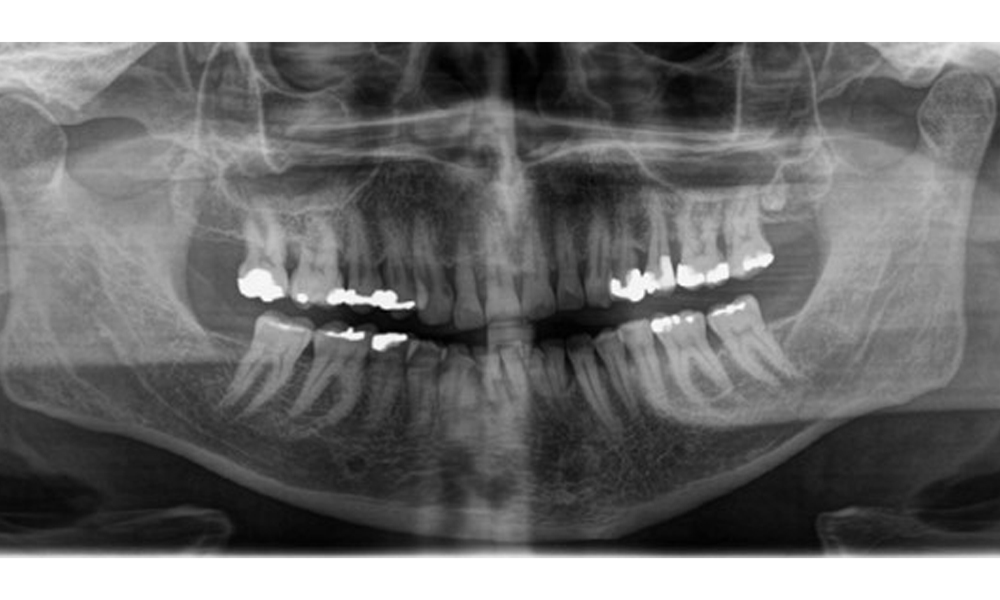

Radiological findings

There is fully dentulous adult dentition with generalized bone loss of between 20-50% and multiple areas of vertical bone loss. Radiological examination revealed no visible caries. (Fig. 7)

Panoramic X-ray image showing generalized radiological bone loss with multiple vertical defects of between 20% to 50%. © Dr R. Krapf

Fig. 7 Panoramic X-ray image showing generalized radiological bone loss with multiple vertical defects of between 20% to 50%. © Dr R. Krapf